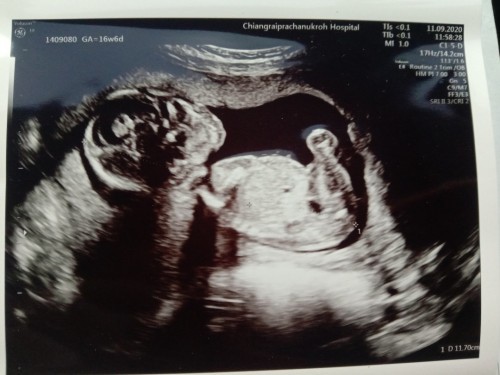

16w6d ลูกสาว

หมอบอกหนูเป็นผู้หญิง มีโอกาสที่หมอจะดูผิดไหมน้า😄 พ่ออยากได้ผู้ชายเพราะคนแรกได้ผู้หญิงแล้ว